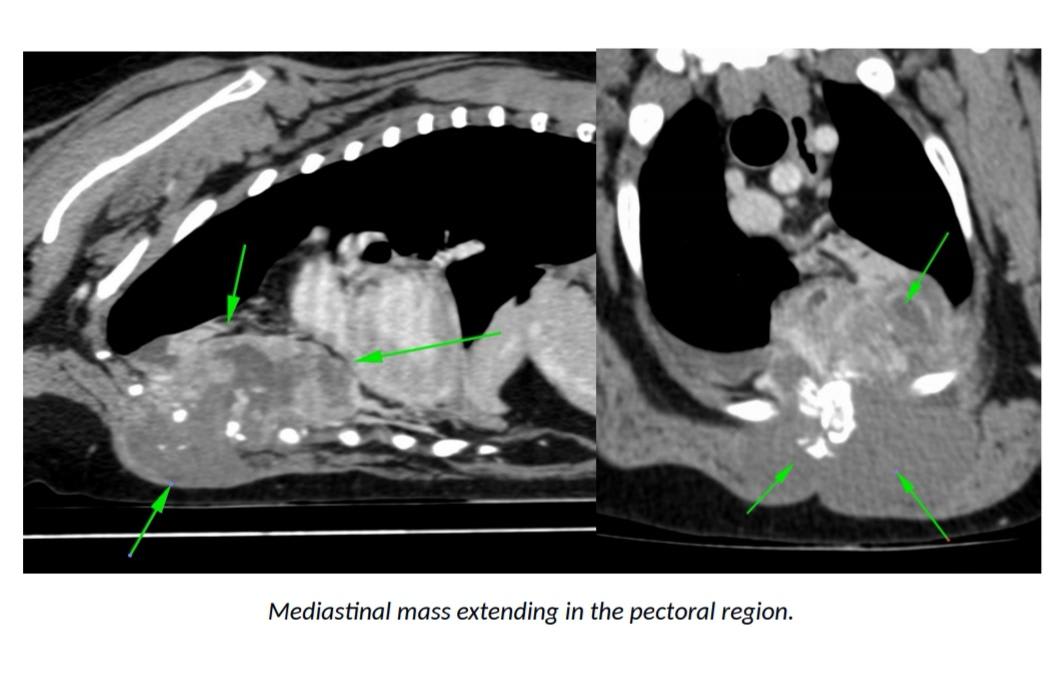

I'm sorry Yogi has a mass! From the images you provided, it looks like he has a mass in his mediastinum that has spread into his pectoral muscles, fluid in his right lung, and nodules in the right lung. I would be suspicious that the nodles in his right lung are cancer that has spread from the medilstinal mass. Dogs can have tumors and still appear normal, and then suddenly appear sick. Without seeing him in person I can't say for certain, but these images do not suggest good news for him. I certainly understand your concern about going on holiday and him going downhill while you aren't there. Speak with your vet to get their opinion on how long he may have left. You can decide to not go on your holiday to spend time with him, or you can go on the holiday, but leave him with a trusted friend and plan to head back home right away if things look poorly for him. It's a very hard decision to make, and I'm so sorry you are in this position. First speak with his vet to get a better idea of what he is facing so that you can make a more informed decision. Best of luck, I hope this helps.